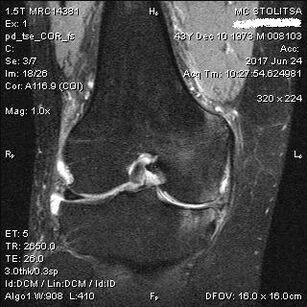

Diagnosis arthrosis sendi lutut berlaku di pejabat ahli rheumatologi atau ortopedis. Doktor meneliti sendi yang terjejas, merapikannya, mendengar aduan dan bertanya soalan tambahan. Melaksanakan beberapa ujian - sebagai contoh, meminta pesakit membengkokkan kakinya atau berjalan beberapa langkah. Kemudian, jika perlu untuk menjelaskan tahap penyakit atau sifat perubahan patologi, dia akan merujuk anda untuk kajian tambahan. Sebagai contoh, untuk tomografi atau radiografi yang dikira.